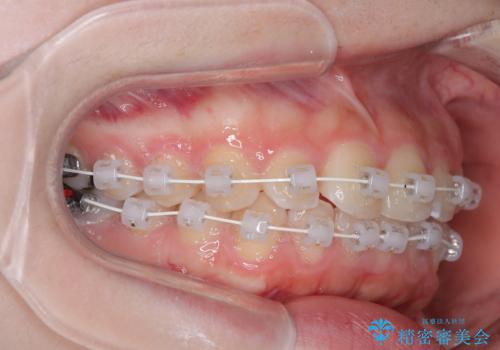

- 矯正装置

- 審美装置

- 上下前歯部のデコボコを気にして来院された患者様です。

叢生は軽度であったため、マウスピースでもワイヤー装置でも対応可能でしたが、マウスピースを長時間使用する自信がないとのことでワイヤー装置にて矯正治療を行うこととしました。

叢生が軽度であったため、僅か半年で装置を除去することができました。